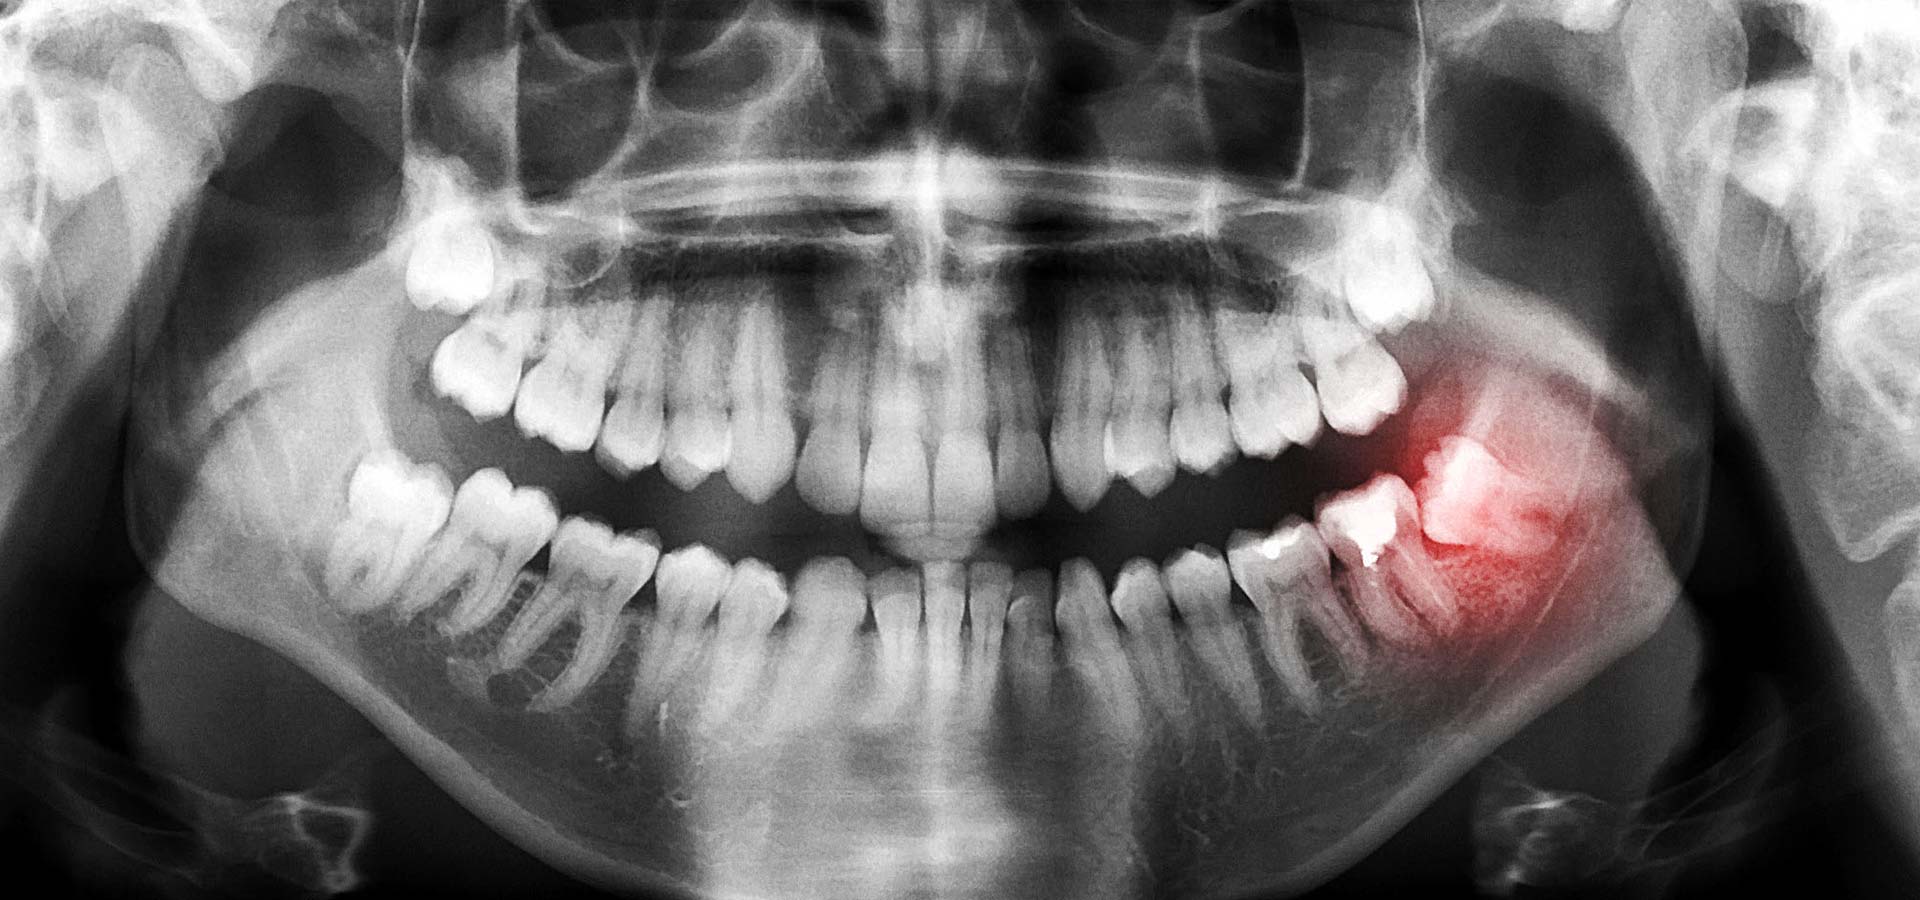

The wisdom tooth sometimes will begin to grow within the gum and this condition is called 'impacted tooth'. An impacted wisdom tooth can cause swelling, infection and pain. Over time an impacted wisdom tooth can have plaque buildup which can then lead to decay. This plaque buildup can lead to irritation in the gums. If left untreated the problem can spread and affect other parts of your gums.

Your dentist will take an X-ray to determine the extent of damage before deciding the right course of action. The extraction method will depend on how many tooth roots are under the gum. In most cases the extraction can be done under local anesthesia.